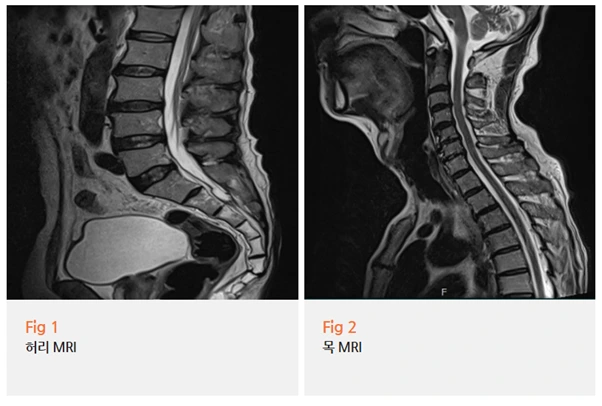

4️⃣ 요추 신경 압박

허리 디스크나 척추관협착증으로 신경이 눌리면

다리를 따라 발바닥까지 저림과 화끈거림이 내려오기도 해요.

허리나 엉덩이 통증을 동반하는 경우가 많아요.